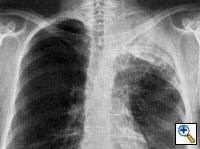

Fig. 18a: Posterior-anterior chest radiograph showing Pancoast tumor in the left apex with destruction of left upper ribs and invasion of the upper thoracic spine. This is a T4 lesion.